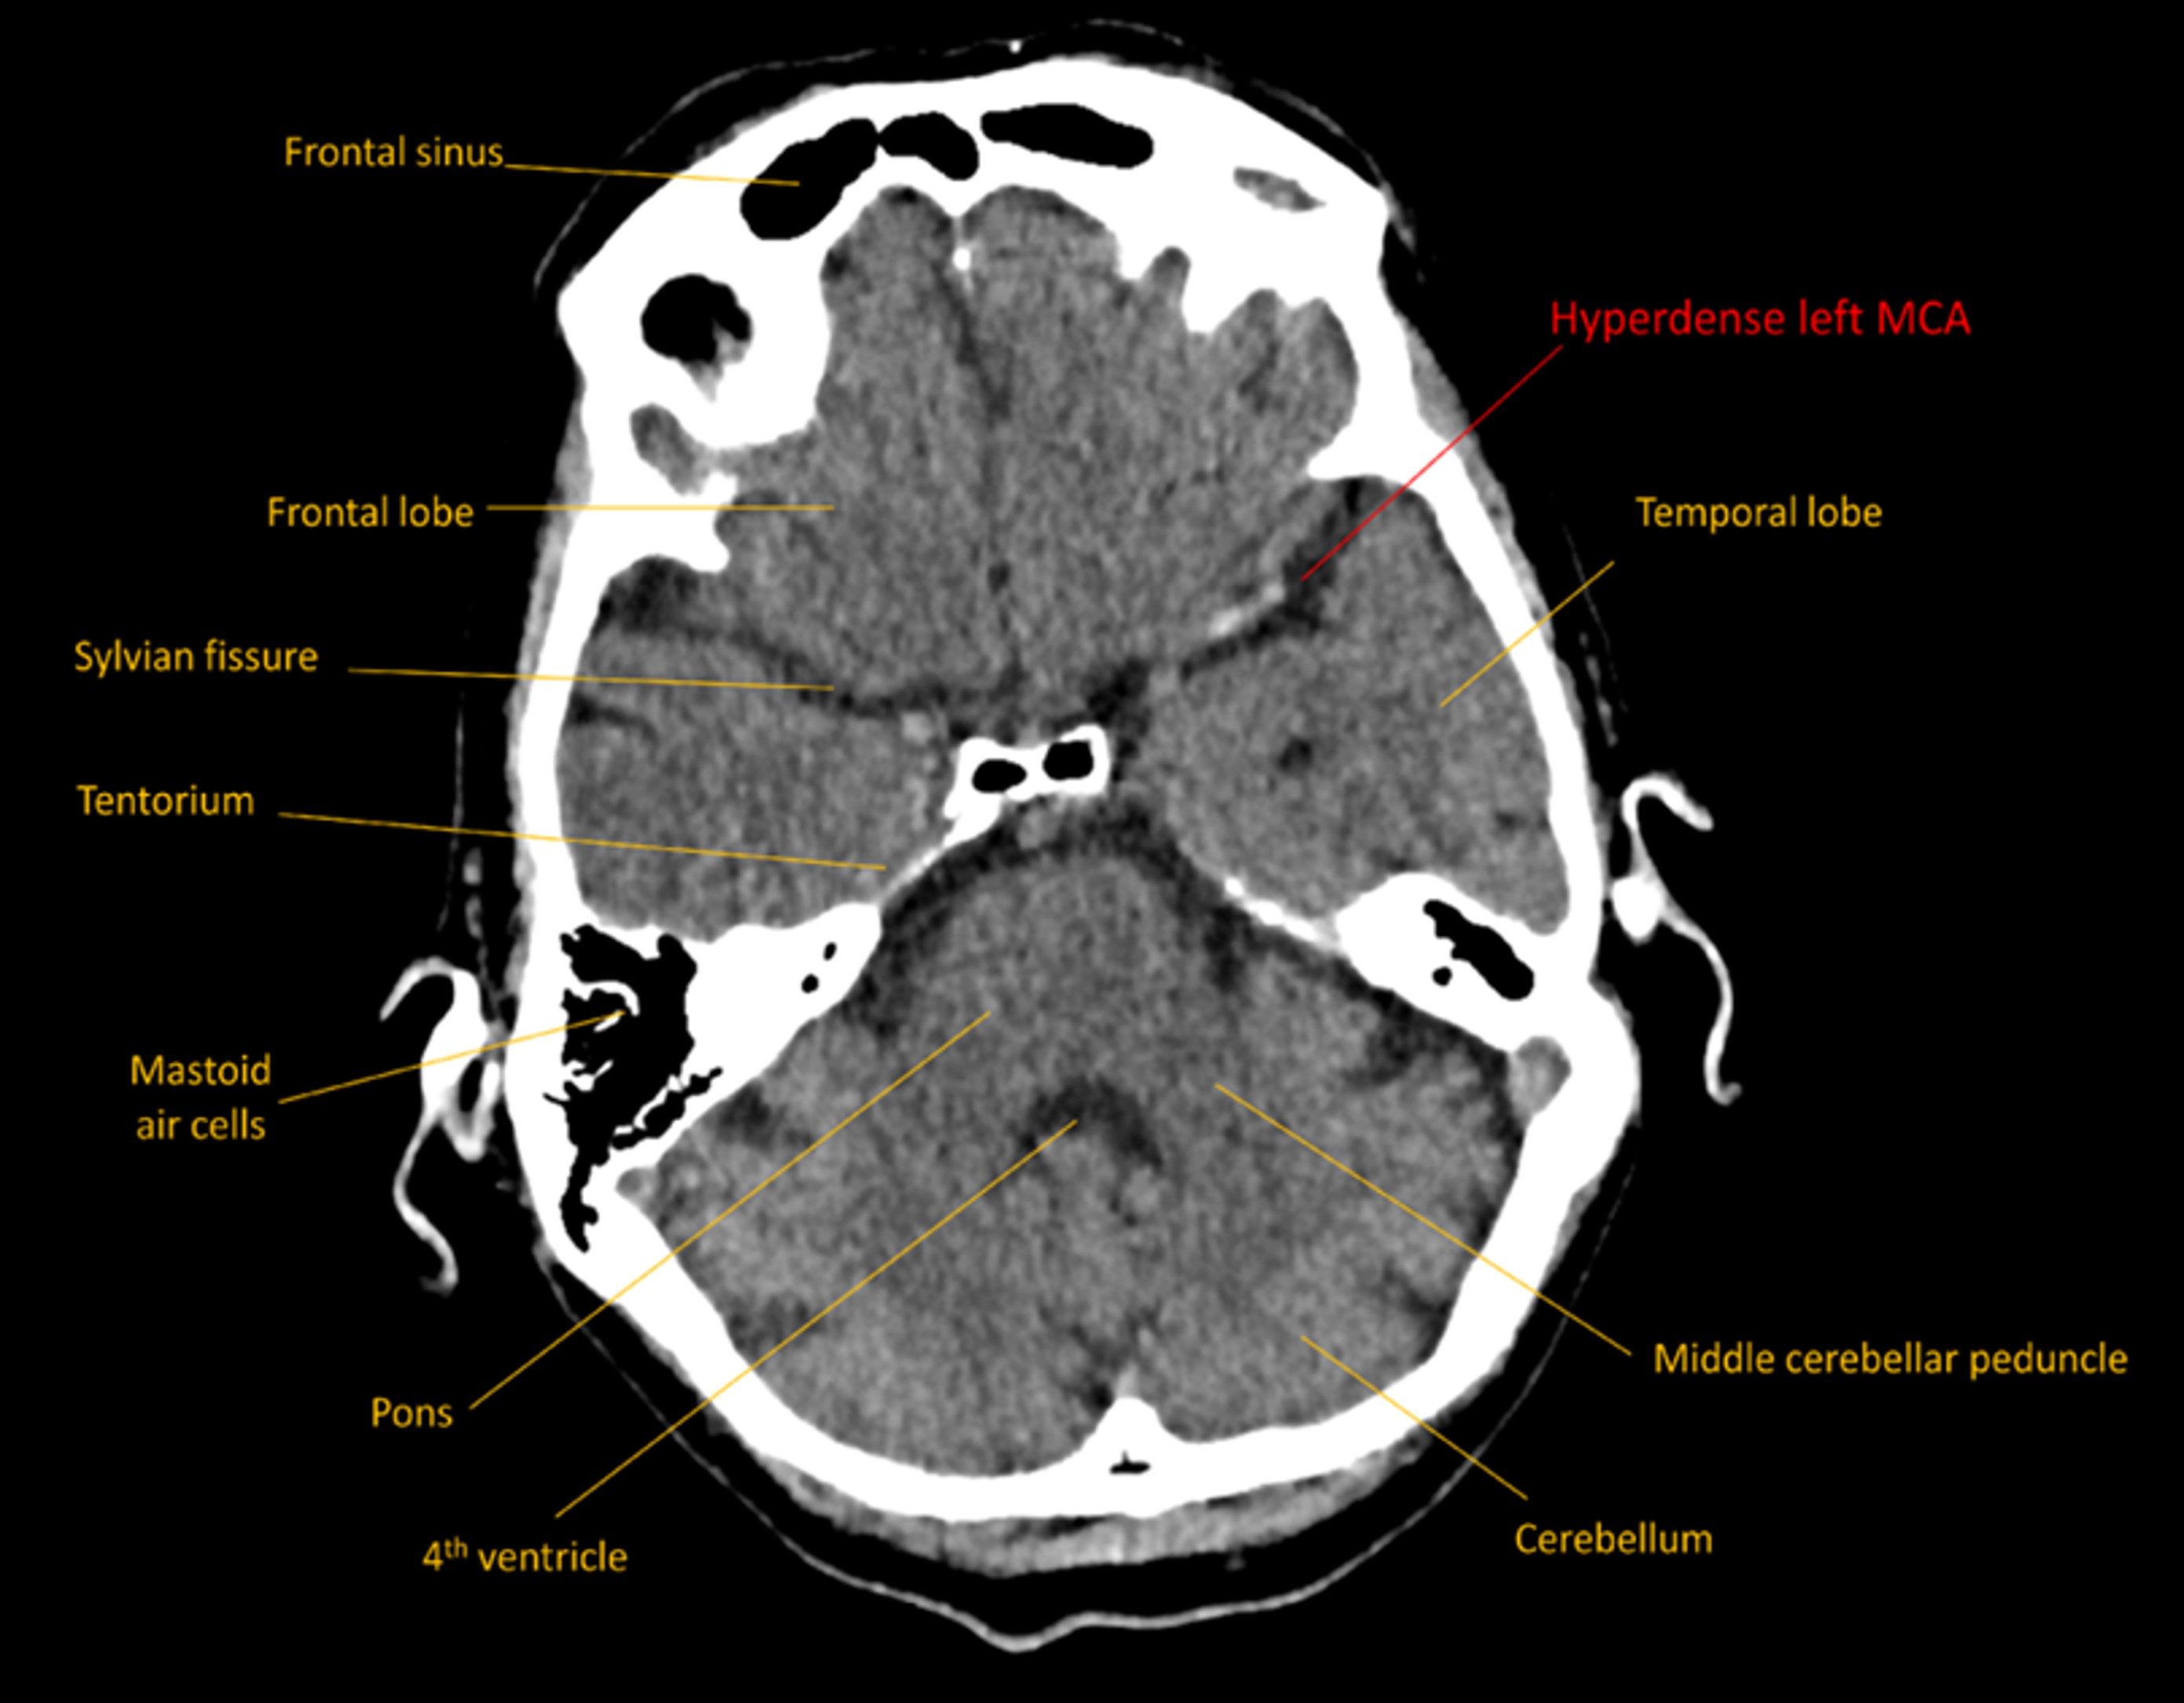

CT imaging showed no signs of acute haemorrhage. There were changes consistent with early ischaemic changes in the left hemisphere in the MCA territory, with subtle loss of grey-white matter differentiation around the insular territory, as well as hyperattentuation in the left MCA, suggestive of an occlusive thrombus.

Hyperdense MCA on CT

This was confirmed on CT angiography, with occlusive thrombus sitting in the distal M1 segment of the MCA, all the way to its bifurcation into superior and inferior segments in the Sylvian fissure.